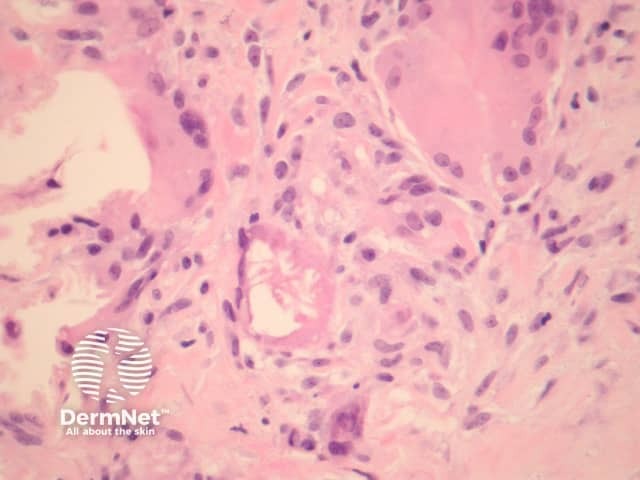

Erythema nodosum histologically represents the prototype of a septal panniculitis. The classic histopathologic presentation of erythema nodosum is that of a septal panniculitis with a mixed cellular infiltrate of lymphocytes, histiocytes, giant cells, and occasional eosinophils and a characteristic absence of vasculitis (figures 1-3).

Miescher's radial granulomata that consist of small nodules composed of spindle to oval-shaped histiocytes arranged around minute slits are thought to be a relatively specific finding for erythema nodosum (figure 4).

Early lesions may be difficult to diagnose on histopathologic features alone. Sections may show oedematous septa containing a prominent mixed inflammatory infiltrate, and minimal fibrosis. As the lesions evolve, there is neutrophilic infiltration followed by chronic infiltrates, granulomas and septal fibrosis.

Small vessel vasculitis (or venulitis) may be seen in early lesions.